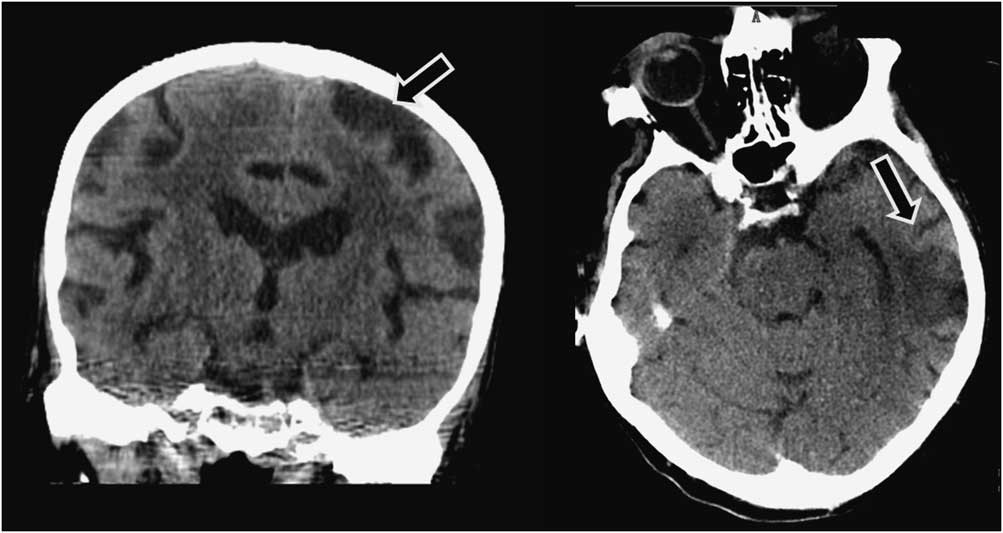

A 91-year-old man was admitted to our hospital with an acute right-sided hemiplegia and somnolence, which had appeared the day before. On admission, myoclonic jerks of the right hemibody were noticed, which promptly stopped after levetiracetam (1000 mg intravenous) administration. His medical history was notable for severe Alzheimer's disease (diagnosed 22 years earlier), chronic vascular encephalopathy with parkinsonism, moderate renal failure, and pancreatic carcinoma. The head CT scan showed ischemic lesions in the left hemisphere, more prominent in the fronto-parietal and temporal lobe, with marked chronic vascular encephalopathy and leukoaraiosis (Figures 1 and 2); the radiological features of the left temporal hypodensity were suggestive of a subacute cerebral infarction. The day after the admission, continuous involuntary contractions of the trunk were noted. Neurological examination showed continuous involuntary and rhythmic jerks involving the abdominal muscles, not spreading to other parts of the body (video). The electroencephalogram (EEG) (Figure 3) revealed rhythmic epileptiform discharges of triphasic/diphasic morphology admixed with polyspikes confined to the left hemisphere (Supplementary material). The most prominent epileptiform abnormalities were localized, over the left posterior temporo-parieto-occipital area. Equipotentiality of epileptiform discharges occurred between electrodes P3 and O1, sometimes with maximal amplitude over O1>P3≥T5>T3, C3 (more evident in referential montage). There were also independent epileptiform discharges located anteriorly, close to the anterior Sylvian region in the left fronto-temporal area, sometimes showing phase reversal at F7 or equipotentiality between F7 and T3. A periodicity (frequency of about 1 Hz) was sometimes evident in epileptiform discharges occurring in both posterior and anterior regions (i.e., lateralized periodic discharges). The EEG recording also showed brief ictal transitions seen maximally over the left posterior hemispheric structures, especially around T5. Overall, the EEG showed anterior and posterior areas of epileptogenicity, more marked in the left posterior temporo-parieto-occipital region. The myoclonic movements were not synchronous with the rhythmic epileptiform discharges. A concomitant electromyographic recording of the muscles of the abdominal wall showed bursts of quasirhythmic asymmetric polymorphic motor potentials of the right abdominal recti muscles, with a duration lower than 100 ms and a frequency of 0.5-1 Hz. The movements attenuated after intravenous administration of lorazepam (4 mg) and levetiracetam (2000 mg), but then reappeared. The patient died of cardiac arrest the following day.

Figure 2 Left: head CT (coronal reconstruction) scan showing a left fronto-parietal ischemic lesion (arrow). Right: head CT (axial) scan showing a left temporal ischemic lesion (arrow); the radiological features of this temporal lesion are suggestive of a subacute infarction.